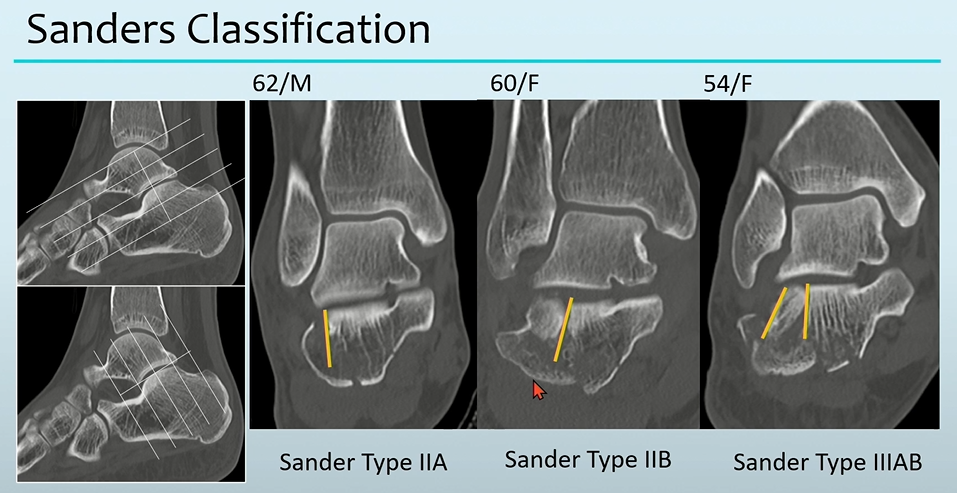

4. Calcaneus Fracture